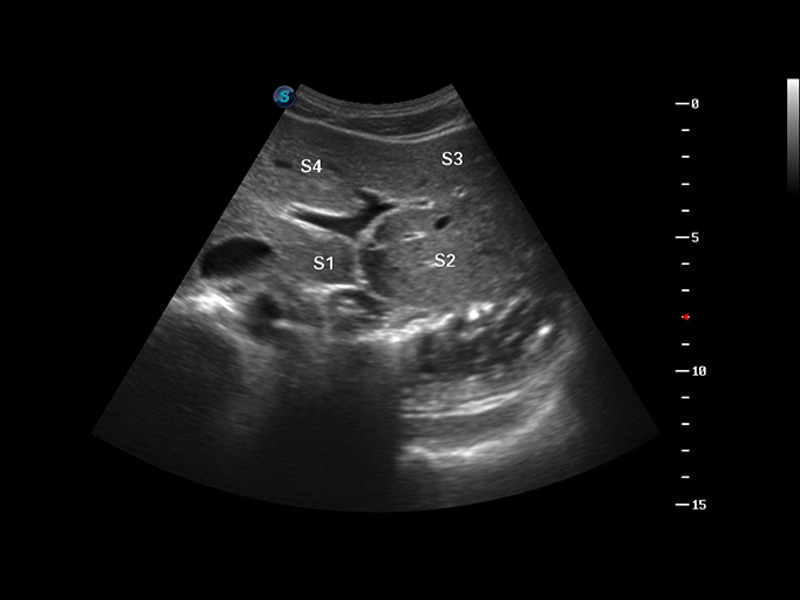

S8 EXP便携式彩色多普勒超声诊断仪是九州酷游研发的高端全身应用型便携彩超。高通道的VIS平台融合可视化(Visual)、智能化(Intelligent)和人性化(Smart)的特点,配以九州酷游自主研发生产的探头大家族,使您能够快速、准确的获得病人信息,提高工作效率的同时减轻疲劳。

成像技术

多波束形成器

μ-Scan微米成像

谐波成像

实时宽景成像

空间复合成像

3D/4D成像